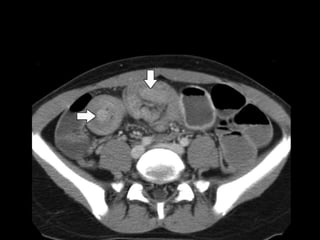

U/S

• Target sign: